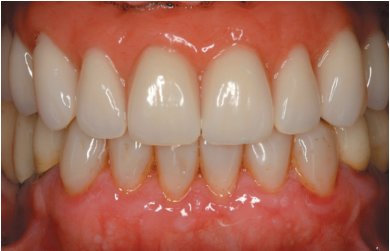

Four months after the initial regeneration of the maxilla surgery a new dental cone-beam is performed, in which the next surgery phase is planned based on the bone gain that has been achieved with the block grafts and the Split technique in two phases. In the images we can see how in the maximum atrophy areas, where the blocks are placed a width has been achieved that triples the initial width (Figures 19 and 20). At the flap opening it is seen as the planification CT images correspond to reality, and also that the area treated by Split in two phases has achieved a crest width that now allows the removal of the transitional implants and the insertion of the new implants in this position, with a better starting and axis situation for the subsequent construction of the prosthesis (Figures 21-22). The implants are inserted and a temporary prosthesis of progressive load is made supported on the implants placed in the first surgical phase. In this way, the patient can have a fixed prosthesis on

implants that will serve to shape the provisional ones in terms of aesthetics and function before the final prosthesis (Figures 23-24).

After four months the loading of the inserted implants in this second surgical phase is carried out. Again, a second provisional prosthesis of progressive loading is chosen, elaborated in the same way as the previous ones. three months aft er the occlusion is prepared for the manufacture of the fi nal prosthesis, so the prosthesis is transformed into a metal-ceramic prosthesis, screwed on transepithelial made by CAD-CAM (Figures 25-26).

The pati ent has recovered the requested functi on, as well as the correction of the occlusion of the complete prosthesis, which presented a right lateral cross bite with decrease in the vertical dimension at the beginning of the treatment. The patient comes to her review and the treatment remains stable as shown in the images taken after 10 years of follow-up (Figures 27-28).